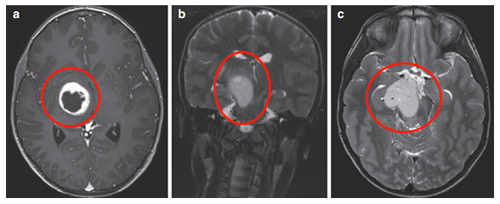

(图6a、b)轴位MRI造影剂及冠状面T2-WI显示一个环形增强的右侧丘脑结节肿瘤。

(图6)

肿瘤累及内侧颞结构(图6c),Rutka教授考虑根据其病情进展制定综合治疗方案,先行经颞中回经脑室入路次全切除肿瘤,组织学为WHO I级毛细胞星形细胞瘤,BRAF重复融合状态为阴性。免疫组化检测BRAF V600E、H3K27M阴性。基因测试证实了NF1基因的变异。术后严密随访患儿术后情况。